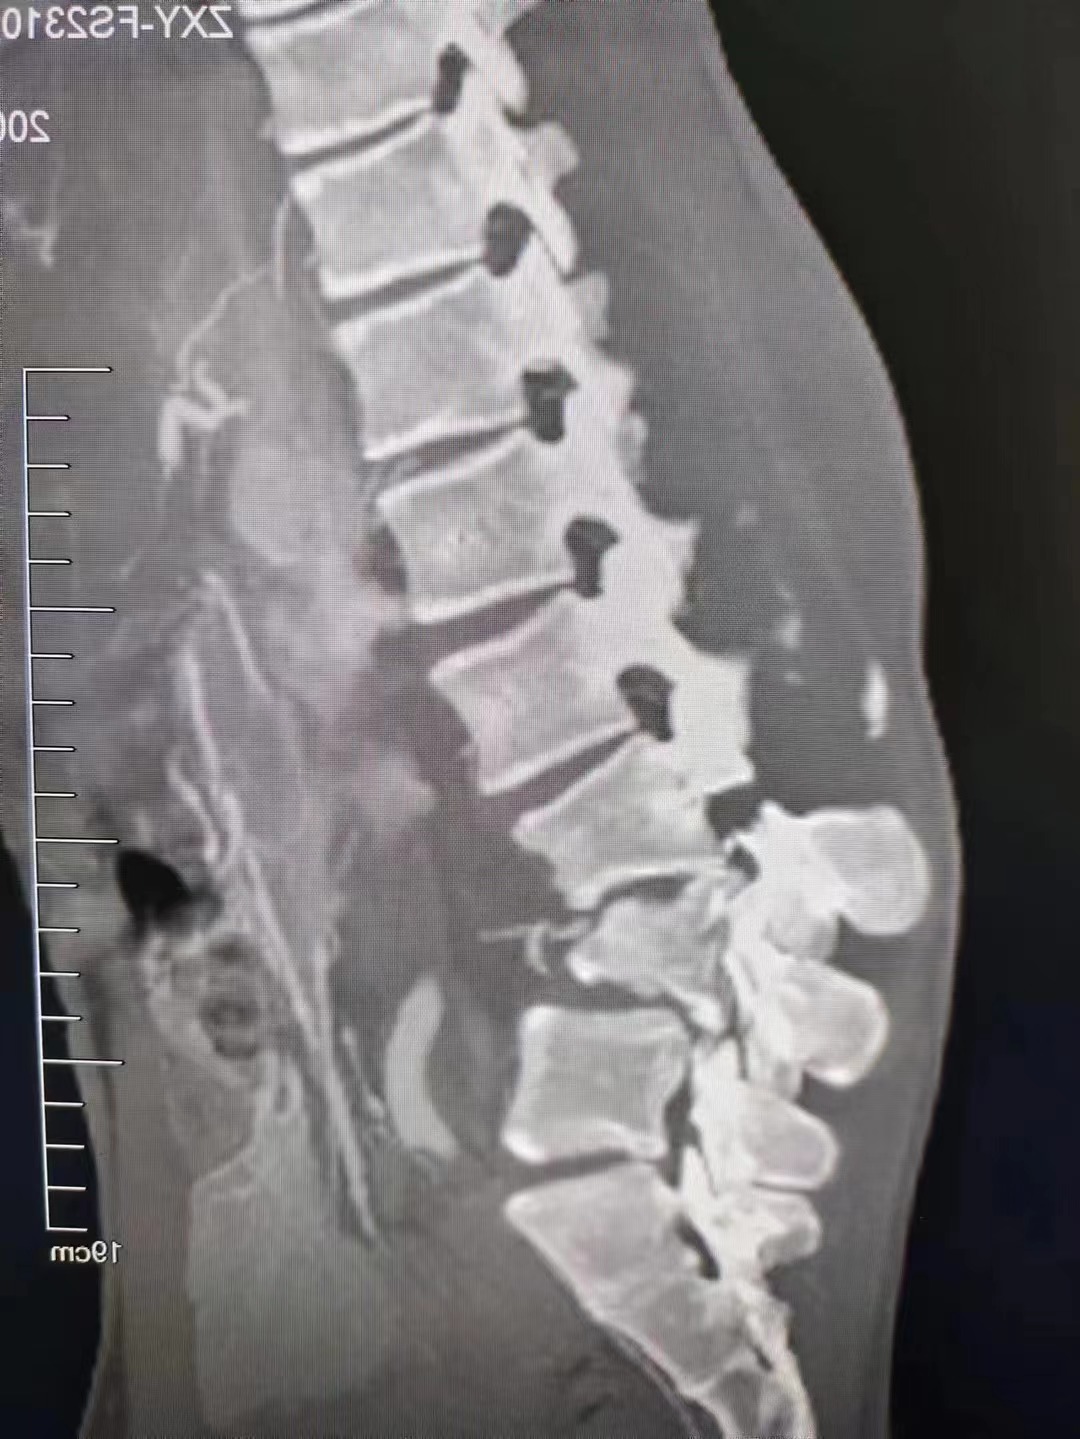

腰椎骨折,钉棒固定,找不到骨折痕迹

50多岁男性,1周前外伤后腰1压缩骨折,术中通过钉棒撑开高度即刻恢复

17岁的少年,在工地被水泥块砸伤,腰3,腰4爆裂骨折